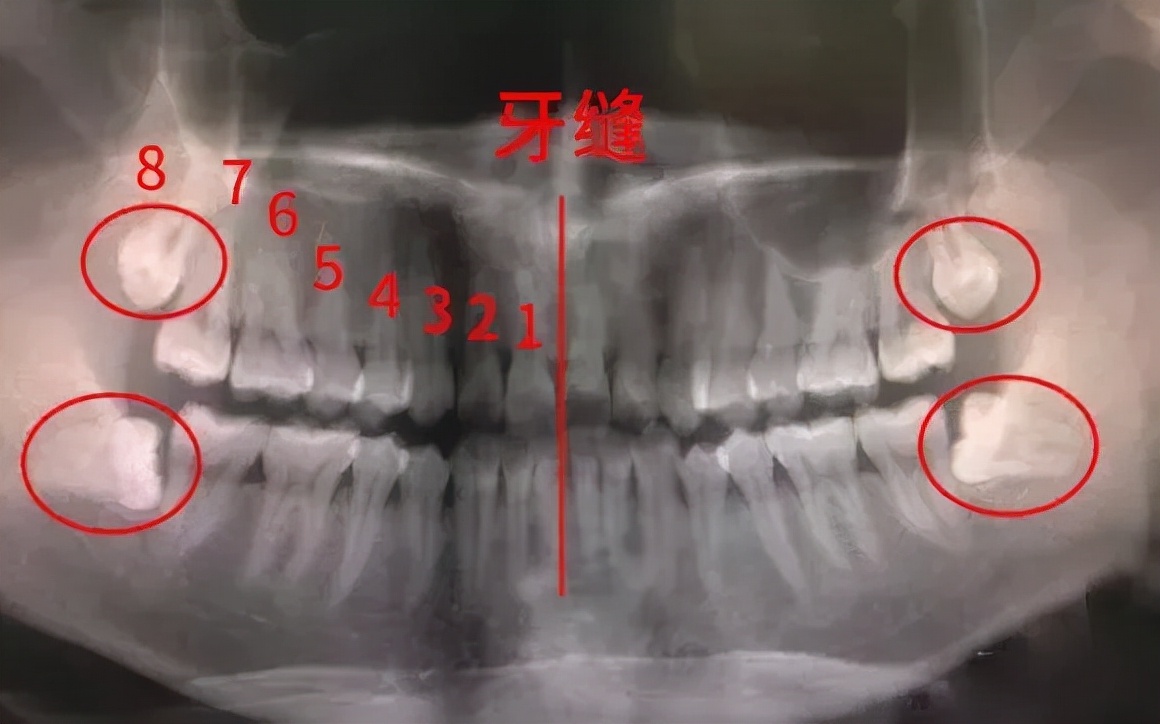

你永远不知道下一秒医生可以从牙齿这些缝隙里面揪出什么:一个月前的牛肉丝、金针菇、小白菜、面包块……

不仅容易藏污纳垢、还有很多清洁死角!久而久之,龋齿、冠周炎等口腔疾病就会找上你。别侥幸,回去看看上面那个血淋淋的案例。

箭头所示处为盲袋,容易积存食物碎屑和细菌

◎ 邻牙的瘟神

本来就没有地儿了,智齿偏要长,还胡乱窜,最惨的是智齿的“邻居”,真是太难了,轻则牙齿表面生成菌斑,重则整个牙为智齿“陪葬”。智齿甚至能把整副牙都挤歪。